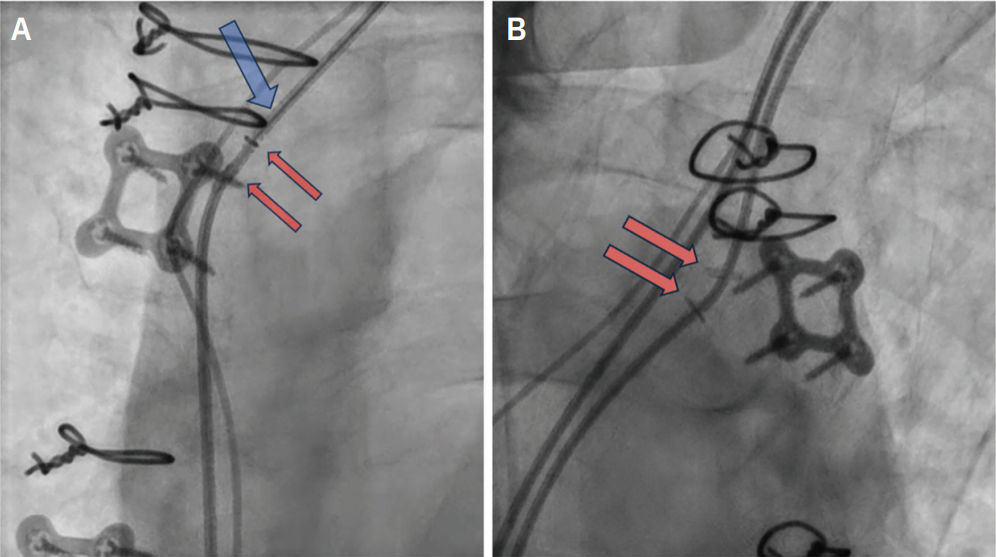

During revision, the stylet encountered resistance along the atrial lead (Figure 4, blue arrow). Fluoroscopic imaging revealed 2 radiopaque clips adhered to the lead

(Figure 4, red arrows). Figure 4B also clearly shows the hemostatic clips. These clips were determined to be the cause of the resistance encountered by the stylet; they were noted to be compressing the atrial lead in the brachiocephalic vein proximal to the superior vena cava junction. The clips were identified as metal hemostatic surgical clips inadvertently placed around the lead during the patient’s valvular surgery. Lead extraction was deferred as the hemostatic clips were extravascular in position. A new atrial lead was successfully placed with no complications and stable parameters. The old atrial lead was capped and abandoned. At 6-month follow-up, the device interrogation was stable with the new atrial lead.